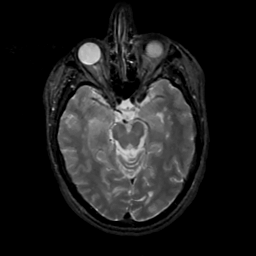

MR Study #4, March 3, 1991 -- Slice #19

[Home][Help][Clinical][Tour 1][Tour 2] Slice 19